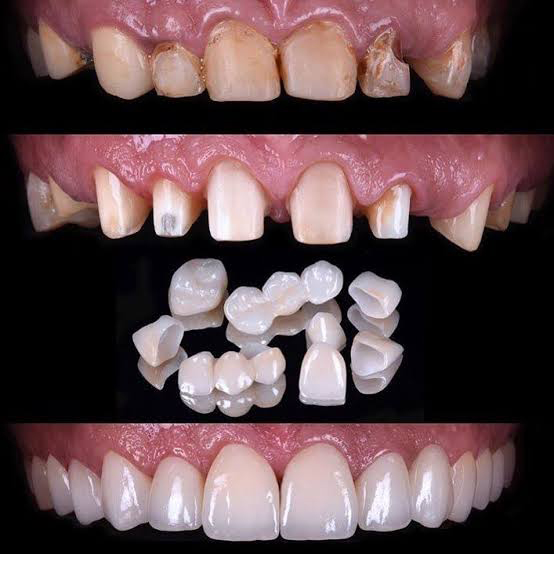

Crowns and Bridges:

Missing teeth can also be replaced by bridges, crowns, inlays etc., depending on the condition of your teeth.

Cosmetic treatment:

Laser teeth whitening, gum recontouring and porcelain/composite veneering are customized to improve each patients’ aesthetic value